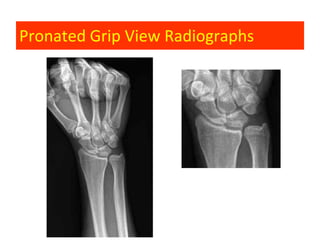

Ulnocarpal Impaction Syndrome

Clinical features:

• Ulnar sided wrist pain

• Associated degenerative changes:

–   Ulnar side of the lunate

–   Radial side of the ulnar dome

–   TFCC central tear

–   Triquetrum- LunoTriquetrum lig.

• Usually positive or neutral ulnar variance

Pronated Grip View Radiographs